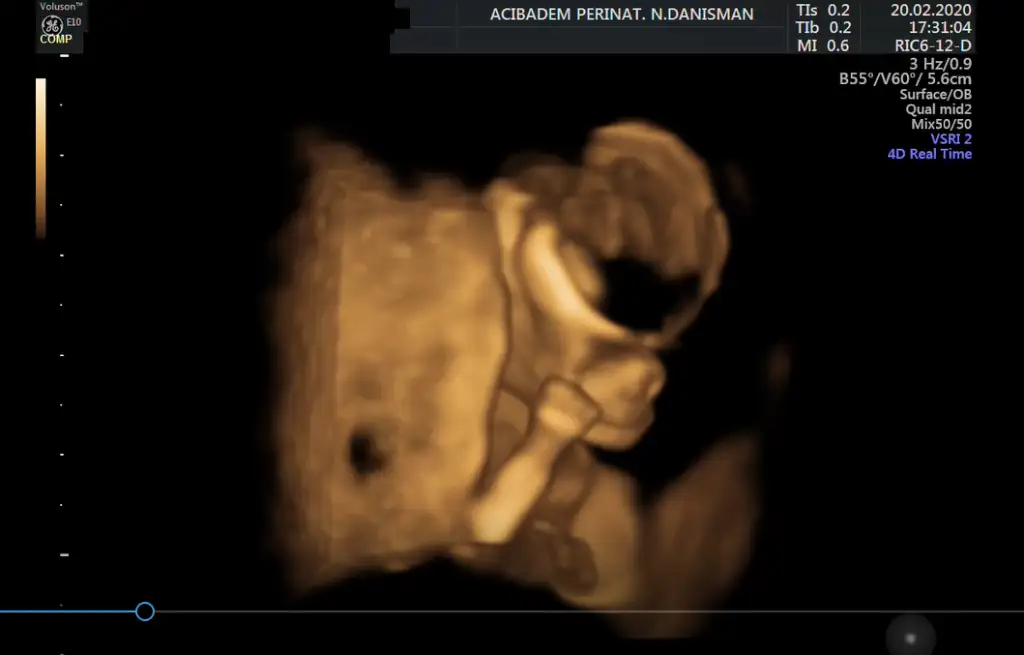

Yaaaa annesi neden dertli diyorsun ki? Dün doktorum bana "Filozof olacak bu" dedi. Benimki de sürekli düşünüyor. Şimdi doktorun verdiği usg videolarını izliyorum. Aman Allah'ım içimde resmen bir dünya var! Allah bize nasıl bir şey bahşetmiş, kafayı yememek elde değil. Minyatür insan!

Eki Görüntüle 2594047 Eki Görüntüle 2594048

Bu güzellik doktorunun dediği gibi tam bir Filozof bir eliyle çenesini tutmuş bir elini yumuruk yapmış..Maşallah maşallah kuzuya Allah esirgesin..

Sagol canim benim, amin 😍 Burada odak noktasi beyin idi. Videodan rastgele ben kestim goruntuyu. 🤪